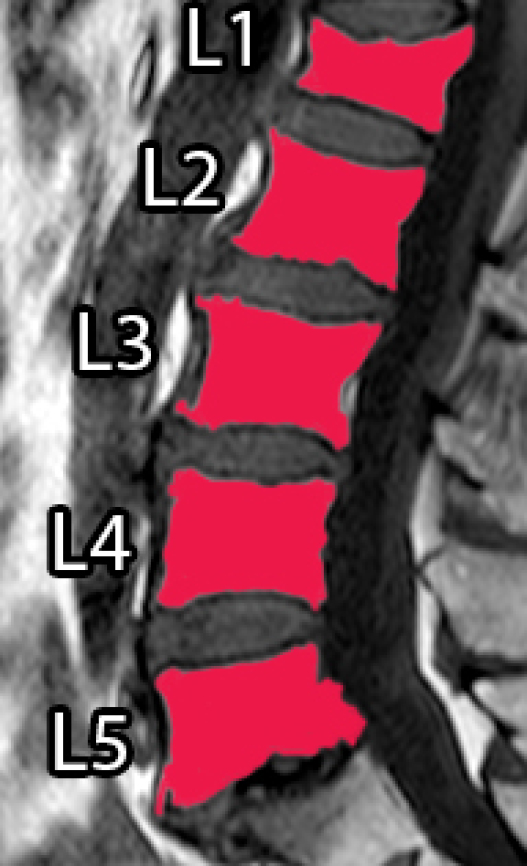

Spinal diseases are quite usual worldwide and can cause significant loss of function and quality of life [1]. A very recurrent disease among older adults is the Vertebral Compression Fracture (VCF), which, in general, is caused by osteoporosis (benign) or bone metastasis (malignant) [2, 3, 4]. In general, VCFs are early detected or diagnosed based on shape or texture using Magnetic Resonance Imaging (MRI) [5, 6, 3, 7]. Usually, a specialist manually segments the Region of Interest (ROI) to aid the diagnose, which can be time consuming and prone to errors, due to inter and intra-subject variability and the subjective judgment that is employed [8].

However, it incorporates expert knowledge gained over several years. Figure 1 shows an example of manual segmentation over five lumbar vertebral bodies (L1-L5).

| (a) Original image | (b) Ground-truth |